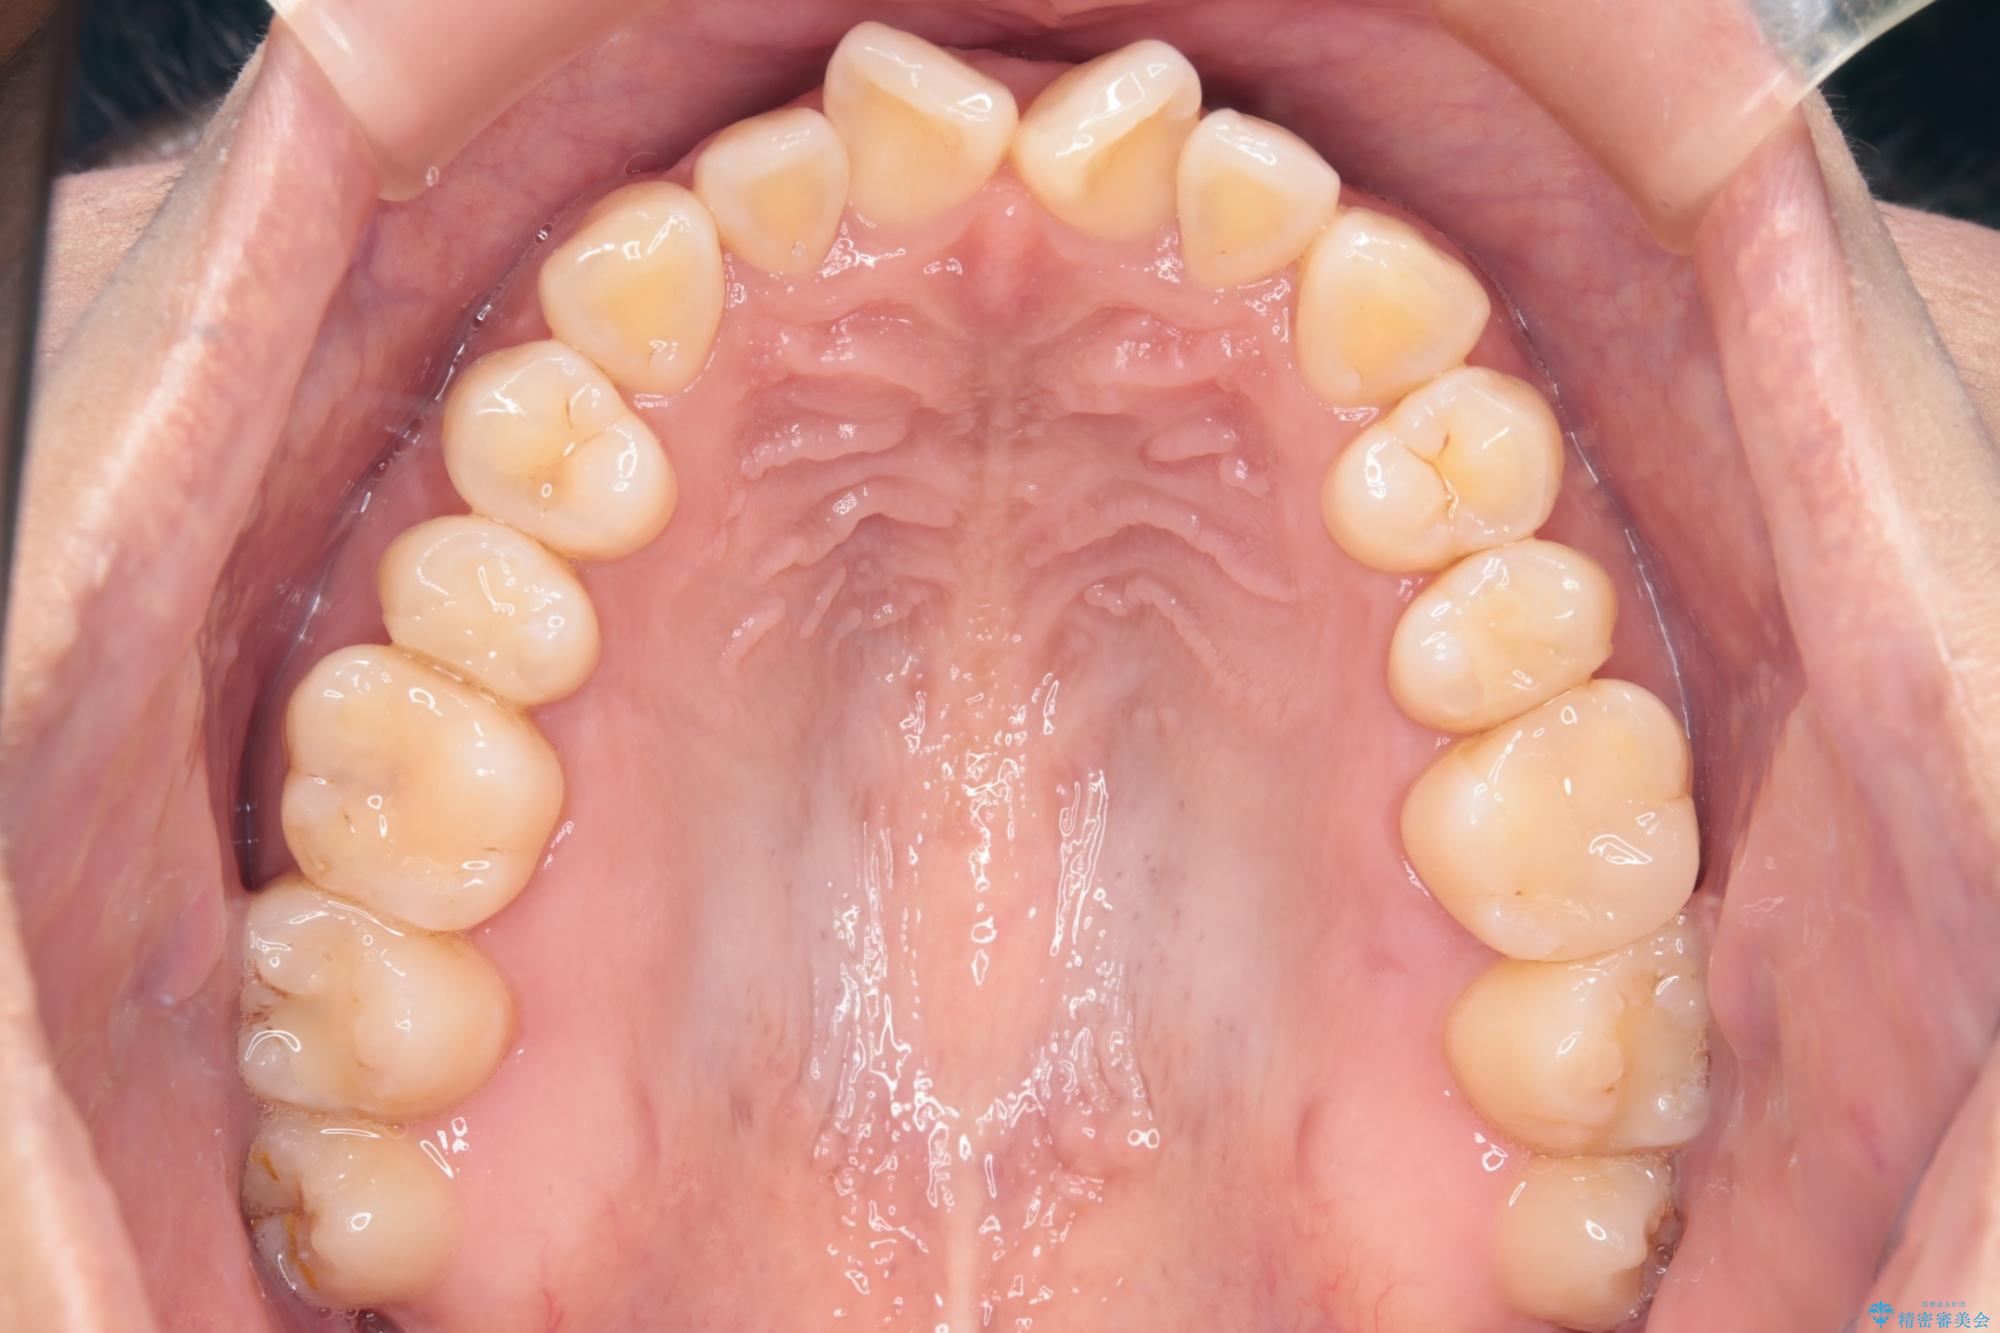

治療後について

かみ合わせを整えるためにゴム掛けも併用して治療を行いました。

患者様にマウスピースの使用とゴム掛けを頑張っていただいたおかげでリファイメント(マウスピースの再発注)も1回で終了することができました。